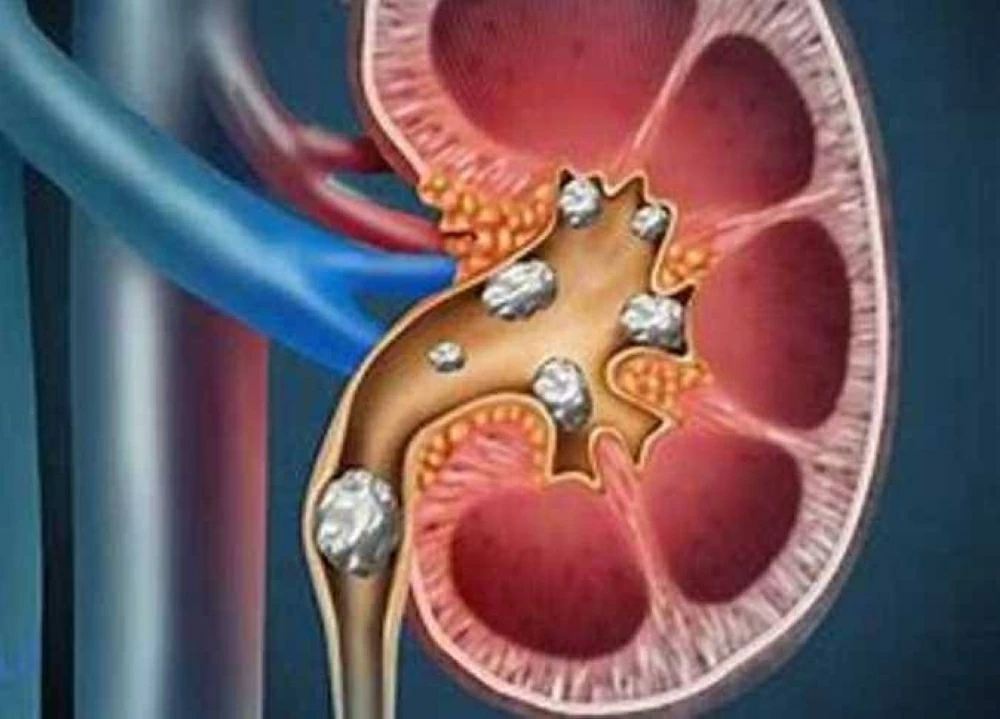

تعد حصى الكلي من المشاكل الصحية الشائعة التى تحدث نتيجة تراكم الأملاح والمعادن داخل الكلى، مما يؤدى إلى تكوّن حصوات قد تعيق مرور البول وتسبب آلامًا شديدة. وقد تختلف الأعراض من شخص لآخر حسب حجم الحصوة ومكانها، لكن هناك علامات واضحة يمكن أن تشير إلى وجود هذه المشكلة.